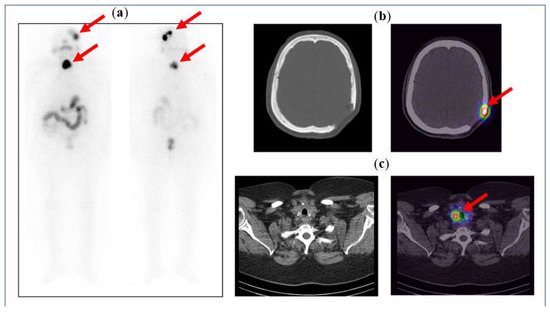

Figure 5 below illustrates the case of a 71-year-old female, known to have follicular thyroid carcinoma and skull bone metastases, after a total thyroidectomy with neck dissection and post-excision of the skull bone metastases. The patient was given a high dose of 5.5 GBq radioactive iodine (RAI) therapy, and the post-therapy scan shows iodine uptake in the neck, which is localised to the residual thyroid tissue on the SPECT/CT images, and iodine uptake in the left parietal bone, localising the residual tumour at the post-operative margins.

Figure 5.

(a) Anterior and posterior whole-body images of the post-therapy iodine scan showing iodine uptake in the neck and the left side of the skull. Physiological tracer distribution is seen in the salivary glands (as pointed out by the arrows), stomach, bowel loops, and urinary bladder. (b) CT and fused SPECT/CT images of the skull showing an osteolytic lesion with tracer uptake along the post-operative margin in the left parietal bone. (c) CT and fused SPECT/CT images of the neck clearly show tracer uptake in the residual tissue in the neck (seen as hot spots on the image on the right).

Figure 7 illustrates the clinical case of an 11-year-old boy with a 3-month history of rhinorrhoea following a head trauma. His clinical evaluation and skull X-rays were normal, and he was referred to the nuclear medicine department for radionuclide cisternography to check for CSF leakage. Under aseptic technique, 125 MBq of Tc99m-DTPA was injected intrathecally, and static as well as SPECT/CT images were acquired. SPECT/CT was able to detect a CSF leakage and accurately localised it to the right ethmoid bone. These findings were confirmed at surgery.

Figure 7.

Planar static images (top row left: axial view; top row middle: coronal view; top row right: sagittal view) show an abnormal focal uptake in the frontal skull region as depicted by the cross. Bottom row: SPECT-CT views localising the uptake to the right ethmoid bone.